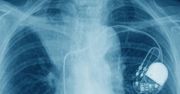

iPhone 12 może wyłączyć rozrusznik serca. Naukowcy ostrzegają

Według nowych badań opublikowanych w w czasopiśmie Heart Rhythm umieszczenie iPhone'a 12 na rozruszniku serca może wyłączyć jednostkę ratującą życie.